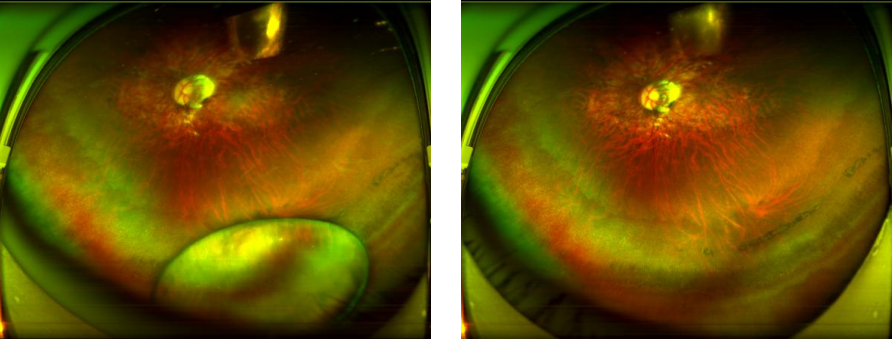

图:小尼手术前后追踪扫描图

目前眼底显微外科微创设备器械不断升级,27G微创玻璃体视网膜器械就是深圳华厦眼科医院在深圳地区最早引进使用的。在经过关键步骤需屏住呼吸的精稳手术操作后,赵铁英院长将小尼的“视网膜心脏穿孔”成功修补封闭,术后两周,小尼的右眼视力已经提高到0.5。